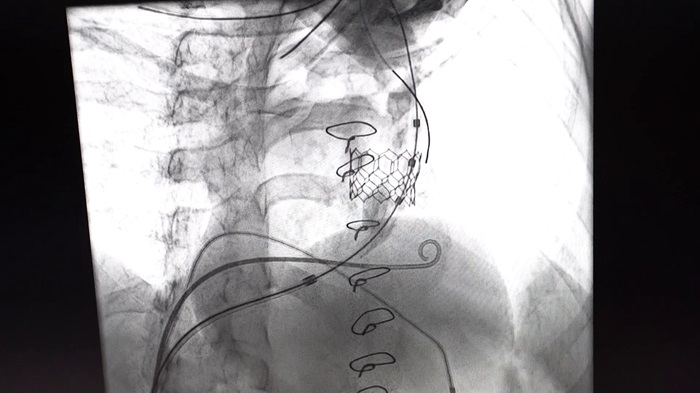

„Исклучително сум задоволен што можев да му помогнам на овој одличен тим во клиниката ‘Жан Митрев’ во исклучително сложената процедура на вградување на транскатетерски залисток на местото на претходно вградена биолошка протеза. Тоа беше направено кај млада пациентка која веќе е оперирана неколку пати и во детството и во зрелоста. Сега дојде ред да се ослободиме од стенозата на нејзината пулмонална артерија. Во ова успеавме со имплантација на валвулата ‘Мајвал 27,5’ преку транскатетерски пат преку феморалната вена. Немаше никакви компликации, резултатот е одличен и се надеваме дека пациентката ќе се опорави брзо и ќе има корист од него во иднина“, изјави д-р Униќ.